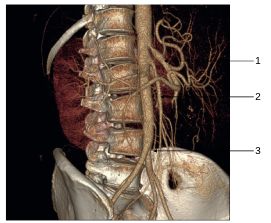

Fig. 35.7 Angioscanner de l’aorte avec reconstructions 3D en vue de trois quarts.

1. Tronc cœliaque. 2. Artère mésentérique supérieure. 3. Artère mésentérique inférieure.

Source : CERF, CNEBMN, 2022.